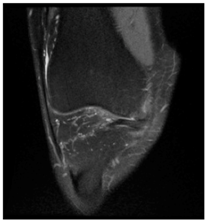

In this section, we present and analyze the results obtained with the proposed method, and compare it to methods proposed in similar works. The proposed watermarking system is implemented using MATLAB and executed on a Windows machine with the following characteristics: Intel R Core i5 processor, 4 GHz, 4 GB RAM, and Microsoft Windows 8 Professional operating system platform. In our experiments, we have used DICOM images of size 512 × 512 pixels as shown in Table 1.

Table 1.

Original images.